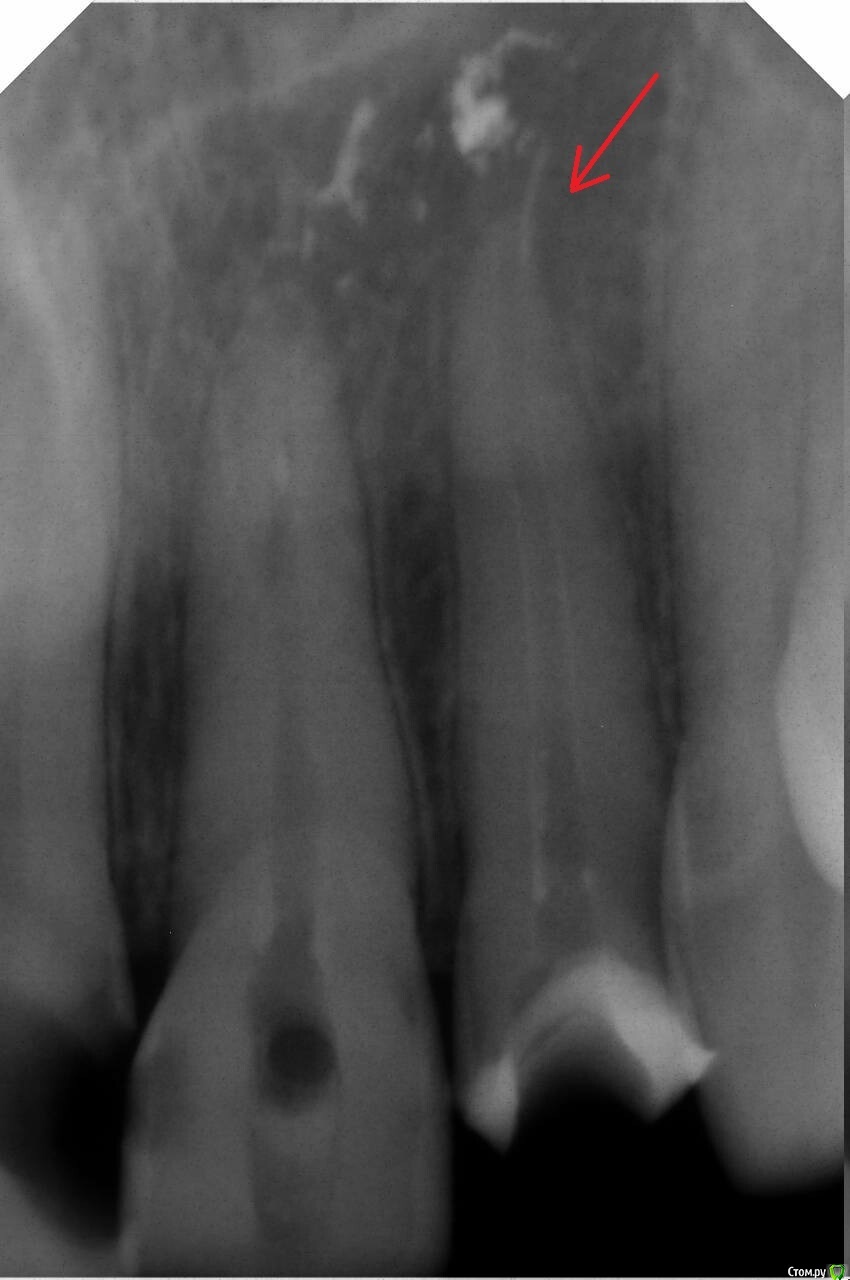

Светлана Прекрасная oierpo Опубликовано 8 ноября, 2020 Поделиться Опубликовано 8 ноября, 2020 Добрый день. Ранее я обращалась к вам по поводу сломанного инструмента в канале. Лечащая врач постаралась убедить меня, что это гуттаперча, а не инструмент.Я нашла врача, которая взялась за периодонтит. Ее методика лечения такая: она мне положила в каналы лекарство, которое выглядит как белый гель, набирала из баночки и назначила уколы в десна линкомицин 2 раза в неделю 10 штук. Сказала, что менять лекарство в каналах вроде больше не будет. И еще сказала, что если это не поможет, то надо удалять эти зубы. Правильное ли лечение? Очень хочу спасти зубы. Ссылка на комментарий

dentikl Опубликовано 9 ноября, 2020 Поделиться Опубликовано 9 ноября, 2020 Добрый день. врач постаралась убедить меня, что это гуттаперча, а не инструмент.а это не гуттаперча? Ссылка на комментарий

St. Опубликовано 9 ноября, 2020 Поделиться Опубликовано 9 ноября, 2020 От того гуттаперча там или инструмент прогноз и тактика сильно не меняются.Показаний к удалению не вижу Ссылка на комментарий